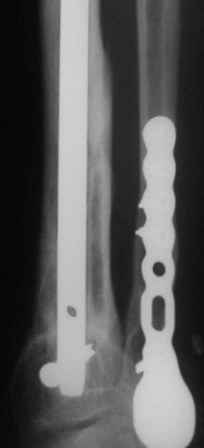

используется гвоздь MetaDiaFix-T, выпускаемый предприятием ЦИТО. В гвозде дистально раполагается овальное отверстие, в которое очень удачно вводятся два винта и заклиниваются между собой, обеспечивая угловую стабильность. Пример использования такого гвоздя привожу ниже.

С уважением, Бекреев Дмитрий. УНИИТО